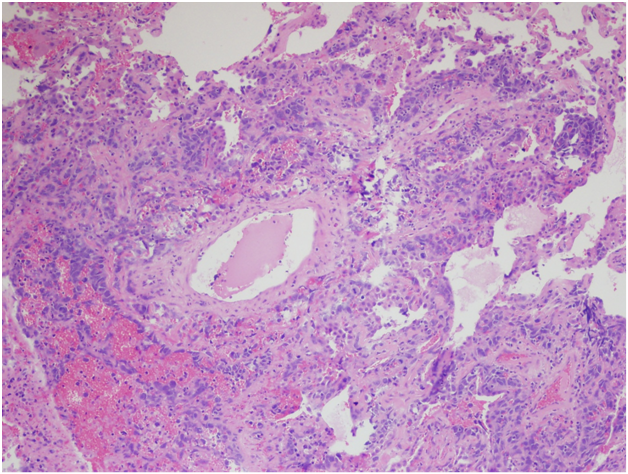

However, the wedge resection of the right lower lobe revealed angiosarcoma with lymphovascular invasion. This biopsy showed highly atypical and large malignant cells with increased mitoses (Figure 2A&2B). The immunohistochemical stains showed diffuse positivity for CD31, CD34, and vimentin (Figures 3A-3C). Stains for AE1/AE3 (Figure 3D), cam5.2, TTF-1, desmin, and OCT3/4 were negative. Along with the clinical history, a final diagnosis of angiosarcoma of the heart with metastases to the lungs was made.

Figure 2A Right lower lobe wedge resection. H&E, 200x

Figure 2B Right lower lobe wedge resection. H&E, 400x